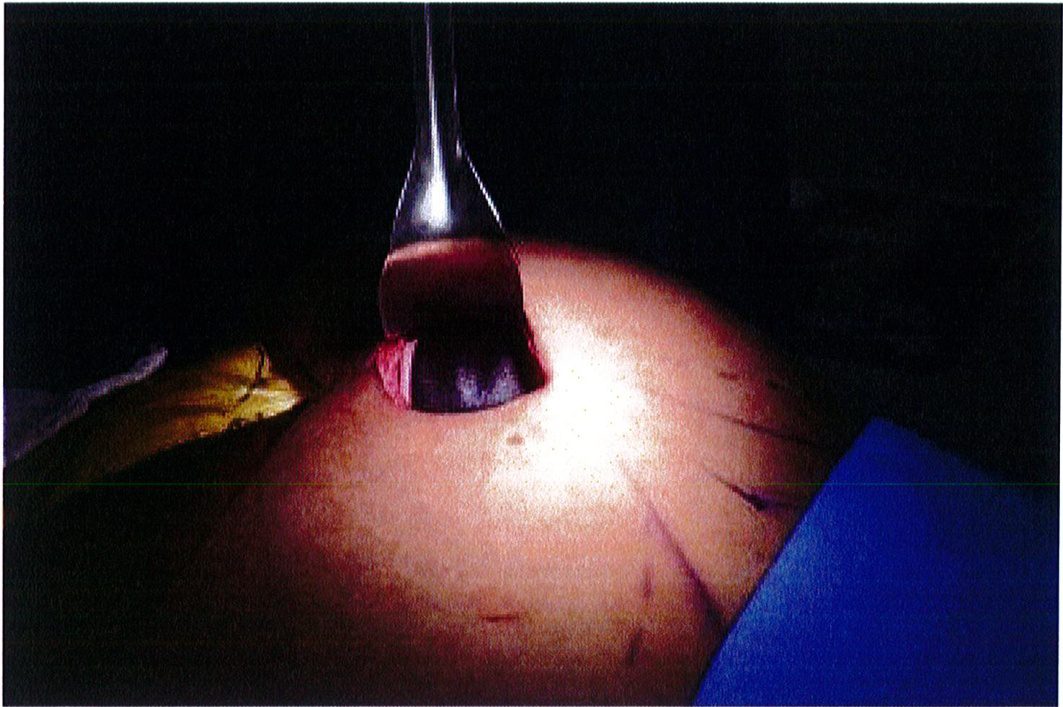

Dụng cụ bóc tách hai đầu tù, hình tròn được sử dụng để phân tách mặt phẳng vô mạch đã được bộc lộ bằng cách tiêm dung dịch trước đó, nhằm bảo tồn tối đa vách và lớp cân mạc. Nên thực hiện bóc tách từ trong ra ngoài, từ trên xuống dưới với một dụng cụ banh có đèn sợi quang (Hình 10). Để tách các vách ngăn, sử dụng một cây bóc tách dài có một đầu nhọn hoặc kéo dài (Hình 11). Các nhánh động mạch mông trên, mông dưới và một số mạch nuôi cho vùng cân mạc được đốt điện. Hãy chắc chắn